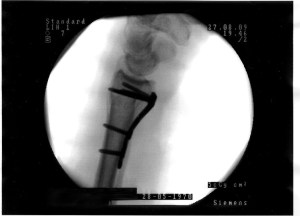

The chronology in a couple of words goes something like this: Happily skating. Crash (snap! snap! crunch-smush!). Pain. OH, F***ING PAIN!!!!! Ambulance, drugs, PAIN!!!!! More drugs, hospital, operation, titanium plate and screws, three days inpatient, two weeks on the sofa at home. Bored, bored, bored. B-O-R-E-D! Harumph.

(Just for the record, the worst part about the whole business was the sound of the electric screwdriver during surgery. Two surgeries, seven screws.)